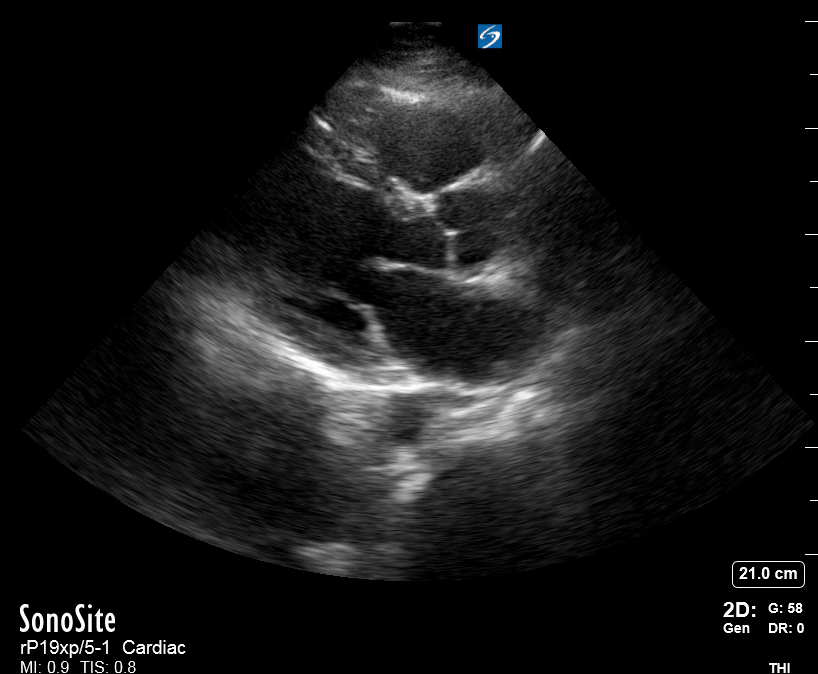

THE VIEWS

The PLAX view is versatile and allows the recognition of multiple landmarks, making it good for visual estimation of LV contractility. It is essential to optimize the view ensuring a true sagittal long axis, as being oblique to the LV chamber may underestimate its size and overestimate its emptying. The PSAX view at the level of the papillary muscles reveals the entire muscular circumference and concentric squeeze of the LV. It is useful to estimate both global function and focal wall motion abnormalities. The A4C view, although technically challenging, provides good insight into the global myocardial function and chamber size.

LV CONTRACTILITY

Qualitative assessment of the LV and visual estimation of Ejection Fraction is based on three parameters:

Endocardial excursion.

Myocardial thickening.

Movement of the anterior leaflet of the mitral valve.

A qualitative assessment is typically categorised as:

Normal (LVEF 50-65%)

Moderately Depressed (LVEF 30-50%)

Severely Depressed (LVEF < 30%)

Hyperdynamic (LVEF > 65%)

SIGNIFICANTLY IMPAIRED / DILATED LV

A severely depressed LV contractility, particularly when paired with a plethoric IVC or lung B-lines, indicates systolic heart failure. Chronically raised afterload can lead to severe dilation of the LV.

In contrast, hyperdynamic states are associated with decreased afterload and are classically found in patients with sepsis or severe hypovolaemia. A hyperdynamic heart should be accompanied by a small, collapsing IVC. Moreover, is essential to remember that tachycardic is not the same as hyperdynamic, as the latter is a measure of contractile activity and emptying. A tachycardic heart is not necessarily hyperdynamic.

E-POINT SEPTAL SEPARATION

Active movement of the MV anterior leaflet during diastole, so it nearly touches the septum, correlates with good LV filling and ejection fraction. This can be assessed objectively by measuring the E-point septal separation (EPSS), which is the distance between the septum and the mitral anterior leaflet either in B-mode or M-mode. EPSS < 7mm is considered normal. EPSS is a good surrogate measure of ejection fraction, but it should be used with caution, as septal hypertrophy and mitral valve stenosis can lead to wrong estimations. In the PLAX view, it is important to have the septum lying horizontally flat on the image, as an oblique orientation may result in an overestimation of the EPSS.